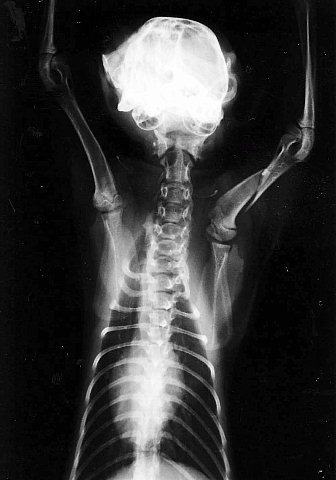

これは子猫でしたが、「鳴き声がうるさい」と言って壁に叩きつけられて骨折しました。

若いカップルでしたが、女性が飼っていた猫に対して男性が行なったという事例です。

手術をして骨は完全に治りましたが、その後は・・・